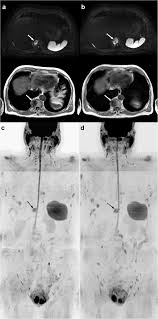

False Positive Diagnosis Of Disease Progression By Magnetic Resonance Imaging For Response Assessment In Prostate Cancer With Bone Metastases A Case Report And Review Of The Pitfalls Of Images In The Literature

False Positive Diagnosis Of Disease Progression By Magnetic Resonance Imaging For Response Assessment In Prostate Cancer With Bone Metastases A Case Report And Review Of The Pitfalls Of Images In The Literature from www.spandidos-publications.com